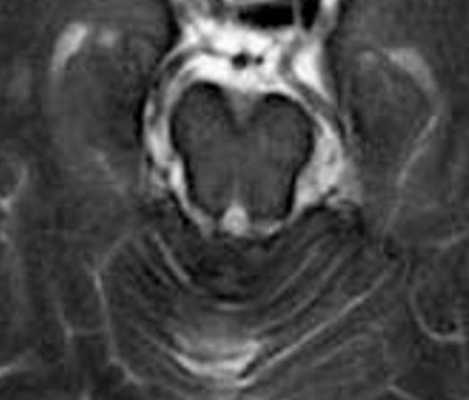

МРТ головного мозга выявляет скопление гемосидерина. Наиболее чувствительны градиентные Т2-взвешенные МРТ. Часто отмечается атрофия червя мозжечка, особенно, видимая хорошо на сагиттальных Т1-взвешенных МРТ.

МРТ головного мозга. Т2-взвешенная аксиальная МРТ через ствол. Тонкое темное кольцо гемосидерина вокруг ствола и в мозжечке. Сидероз головного мозга.